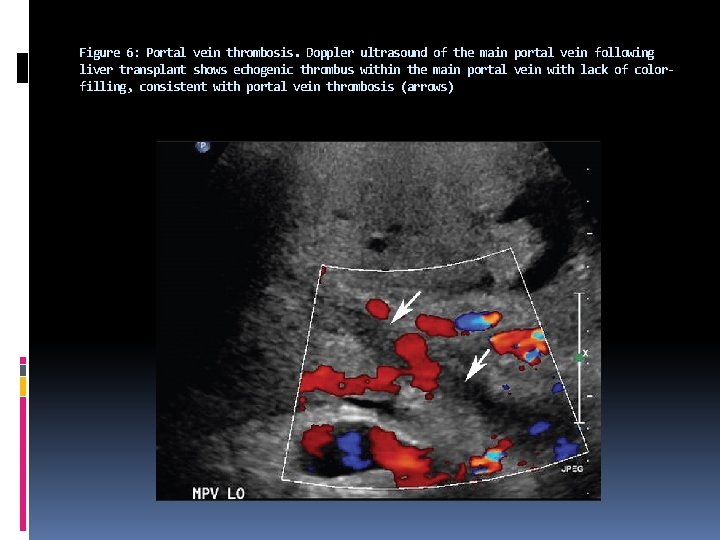

After transplantation, the normal portal vein has antegrade flow. The portal venous velocity is variable and tends to decrease on serial examinations after transplantation. Portal vein thrombosis is the most common portal venous complication after surgery. The thrombus is identified as either anechoic or echogenic material within the portal vein, on gray-scale ultrasound, and no flow is identified on Doppler interrogation. The portal vein should be interrogated with power Doppler so that the slow flow is not mistaken as thrombosis.

In a majority of the patients, portal venous thrombosis is diagnosed within one month of transplantation. It may present with signs of portal hypertension or nonspecific abnormalities of liver function tests. The treatment options in acute cases include catheter-guided thrombolysis and thrombectomy, as well as, anastomotic revision and re-transplantation.

Figure 6: Portal vein thrombosis. Doppler ultrasound of the main portal vein following liver transplant shows echogenic thrombus within the main portal vein with lack of colorfilling, consistent with portal vein thrombosis (arrows)